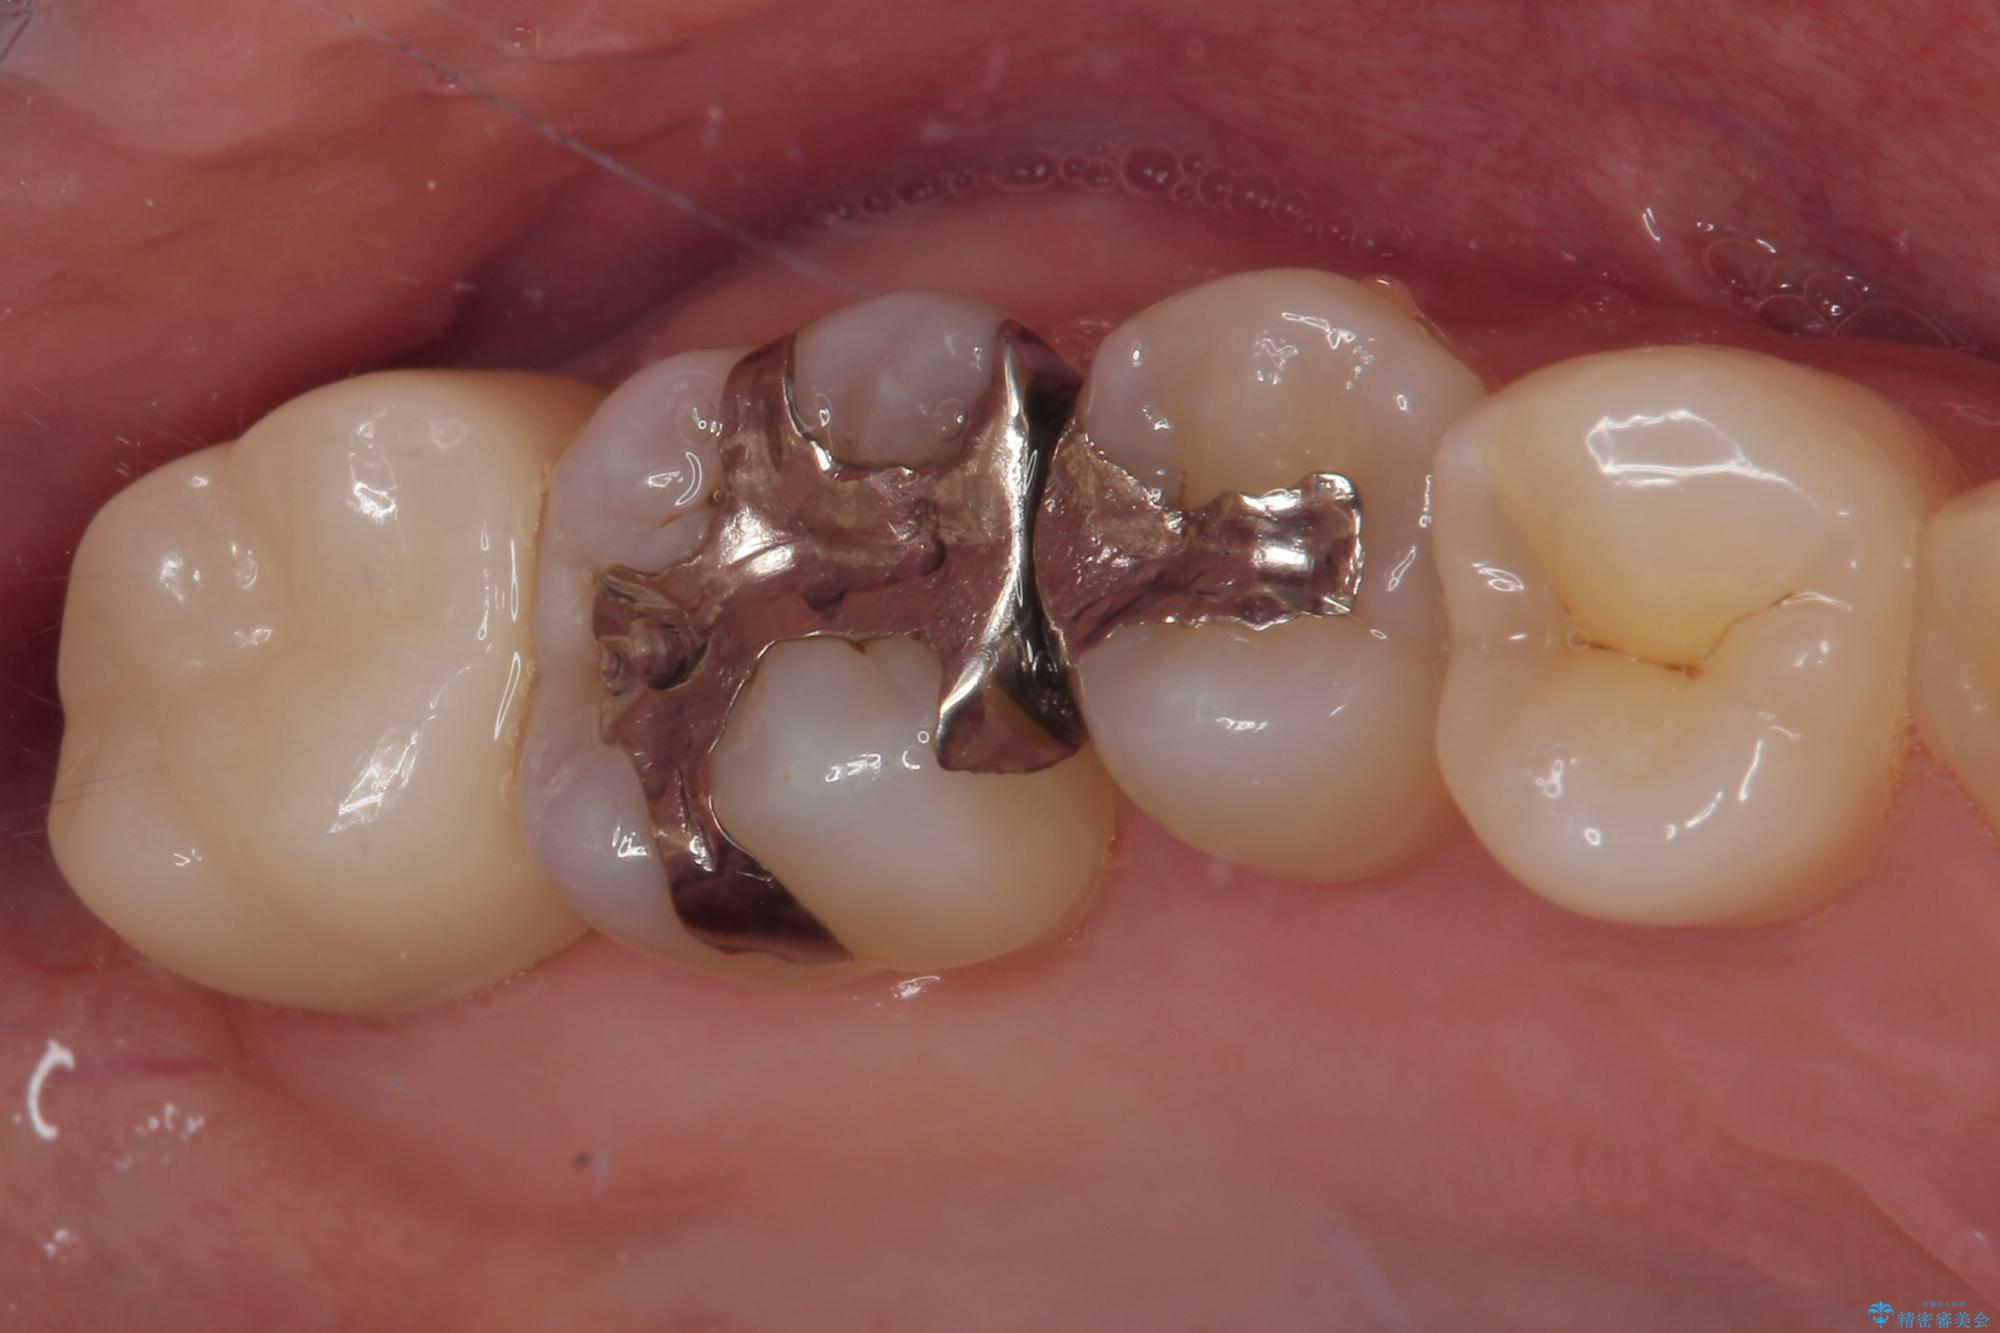

歯列が移動したとはいえ、左右ともに後方傾斜しており、むし歯の除去、形成(形を整える)、型取りの全てが非常に困難な処置となりました。

セラミッククラウンの適合はレントゲン写真からも分かる通り、境界がぴったりと合った、高適合のものとなりました。